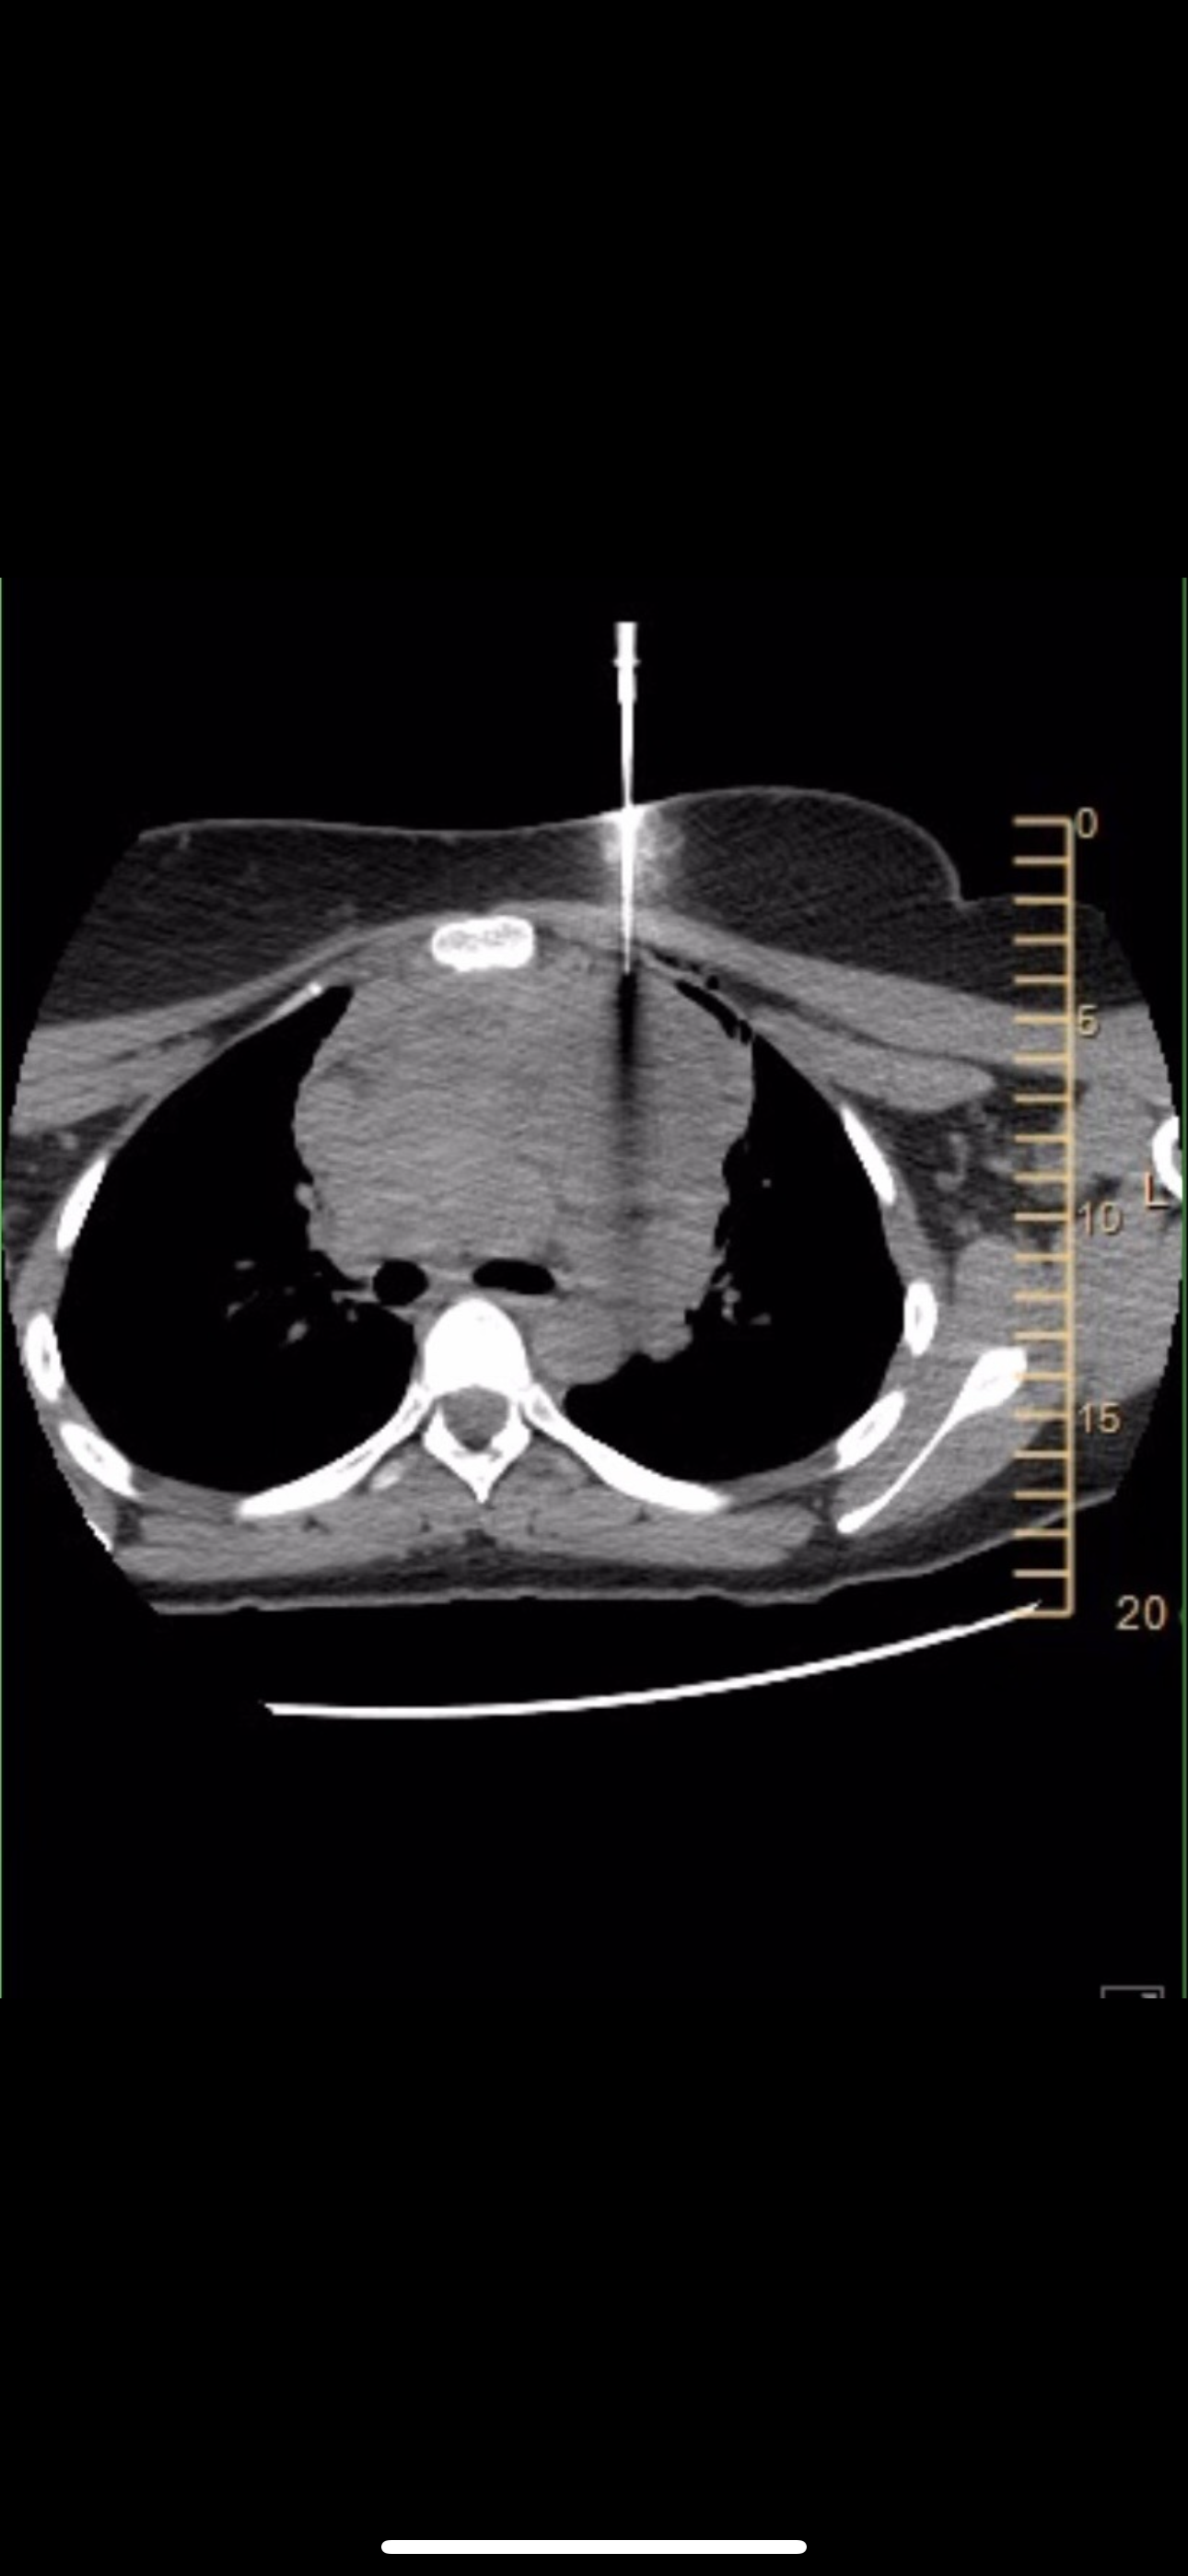

What started as swollen lymph nodes and a trip to immediate care quickly turned into scans showing a tumor the size of a fist in front of her heart!